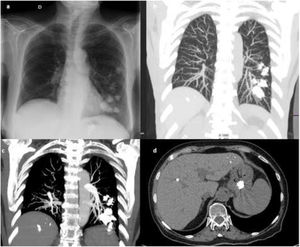

Tras el procedimiento, la paciente comenzó con febrícula, solicitándose una radiografía de tórax (fig. 1a), en la que se objetivaron varias imágenes nodulares hiperdensas en campos medio e inferior izquierdo y en cámara gástrica. Se amplió el estudio con tomografía computarizada (TC) torácica (fig. 1b-c), que confirmó múltiples imágenes de alta densidad en pulmón izquierdo. En la fig. 1d se muestra el contenido hiperdenso en el interior del estómago. Se estableció el diagnóstico de broncoaspiración del material de embolización.

(a) Radiografía de tórax PA. Múltiples opacidades nodulares de alta densidad en campos medio e inferior izquierdo y en epigastrio. (b) TC torácico con contraste reconstrucción MIP. Material de embolización hiperdenso extravascular en campo medio e inferior izquierdo. (c) TC torácico con contraste reconstrucción MIP. Material de embolización hiperdenso bilateral en lóbulo inferior izquierdo, de mayor tamaño que los vasos pulmonares. (d) Material de embolización en el interior del estómago.

Las complicaciones tras el tratamiento de várices gástricas con cianoacrilato/lipiodol son bien conocidas, habiéndose descrito varios casos de embolismo pulmonar1,2. En nuestro caso, el diagnóstico más probable es la broncoaspiración, dado que la paciente presenta restos radiopacos en cámara gástrica, afectación principalmente izquierda (la endoscopia digestiva se realiza en decúbito lateral izquierdo), tamaño de las lesiones mayor que los vasos y correspondencia con el trayecto bronquial.